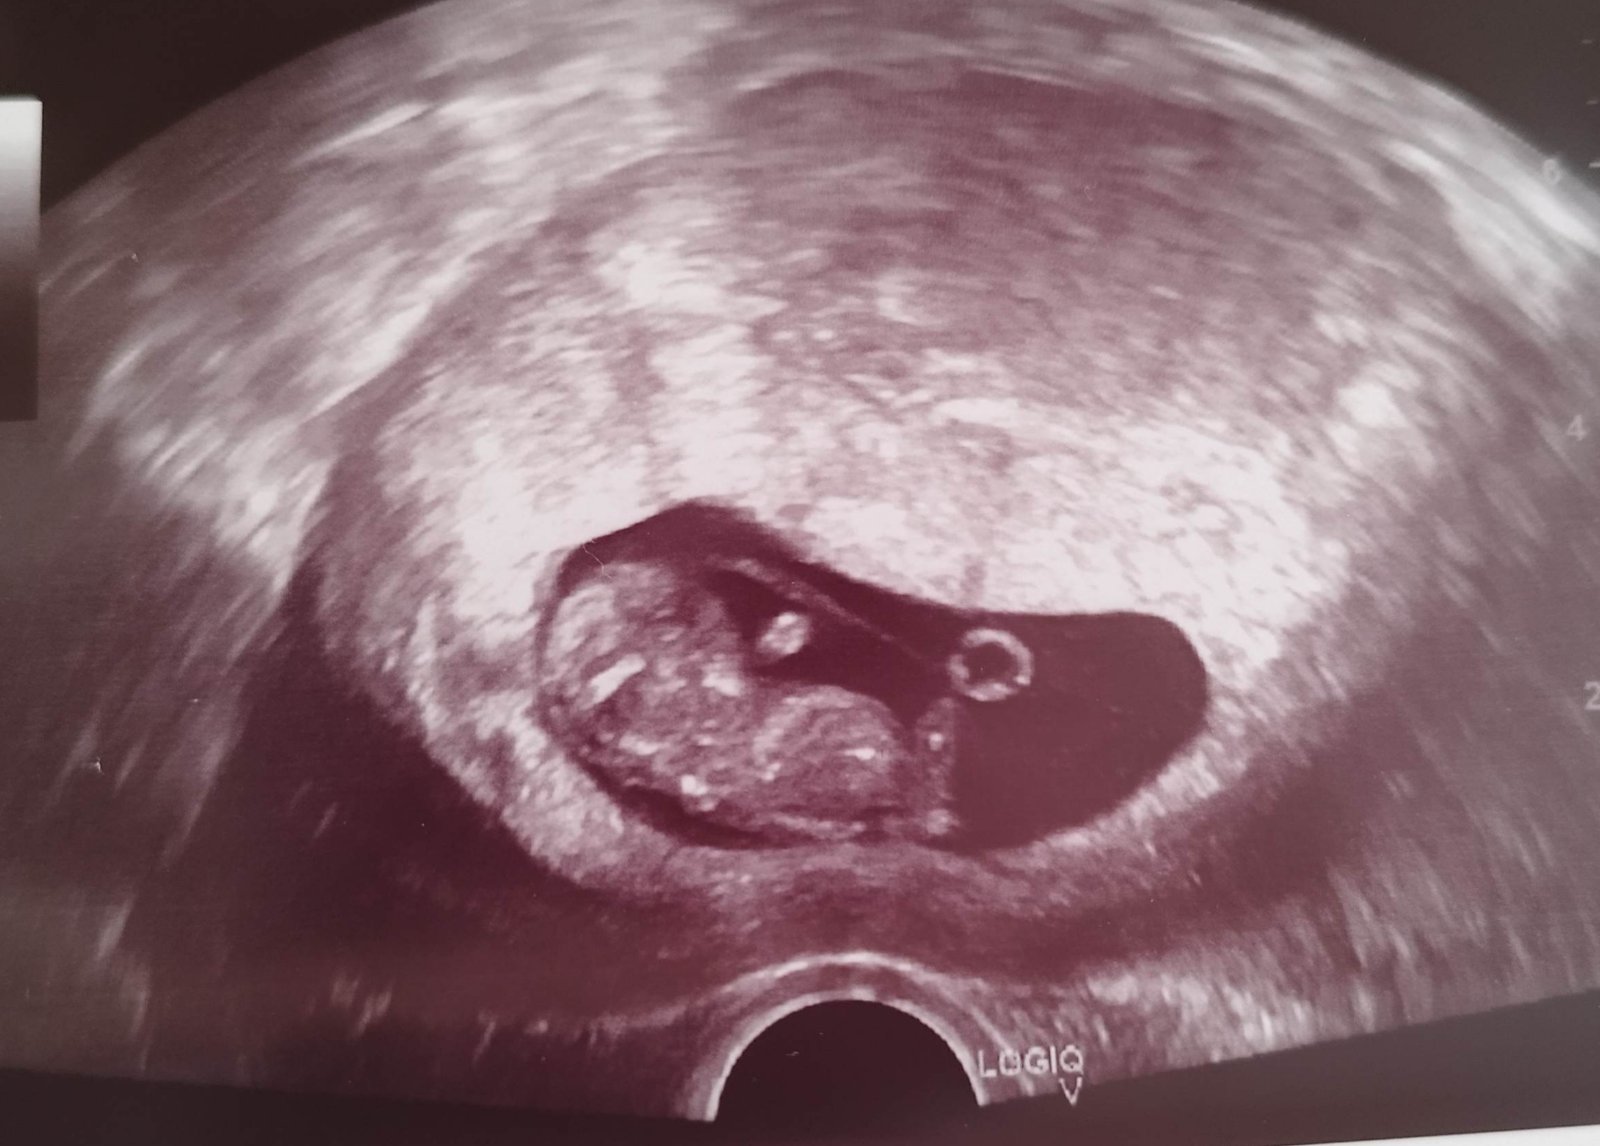

Zdravím všechny, zkouším jestli se tu na téhle diskuzi někdo třeba ještě ozve. 😅 včera jsem byla na prvním screeningu, mám u nej tuhle fotku. V návalu informaci jsem se doktorky ani nezeptala jestli už je něco třeba náznakem vidět. Je mi jasné, ze tady mi to nikdo “nevyvěští” spis mě jen zajímá jestli na fotce je vůbec vidět pohlavní hrbolek. Ja jsem v tomhle poměrně zmatená 😅

@zzuzzanna123 ano, dá se zjistit tak na 85% podle fotky ultrazvuku kolem toho 12. týdnu, ale musí tam být vidět pohlavní hrbolek, což u té tvojí fotky nevidím. Snad příště 🙂

@zzuzzanna123 musel by jit videt pohlavni hrbolek … a tohle je moc brzy, plus neni mimi tak natocene. Nejlepe se to pozna na 1.screeningu